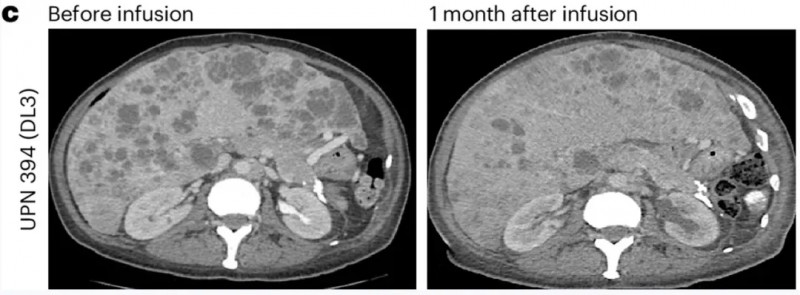

另一例为前列腺癌伴胰腺转移患者(UPN388):输注PSCA-CAR-T前后的CT复查显示,输注前病灶大小为40.2×24.8mm,输注后1个月病变完全消退、已无法测量(详见下图e);尽管因存在骨转移,RECIST评估结果为“病情稳定”,但患者软组织转移灶的放射学表现已有所改善(详见下图b)。

▲图源“Nature Medicine”,版权归原作者所有,如无意中侵犯了知识产权,请联系我们删除